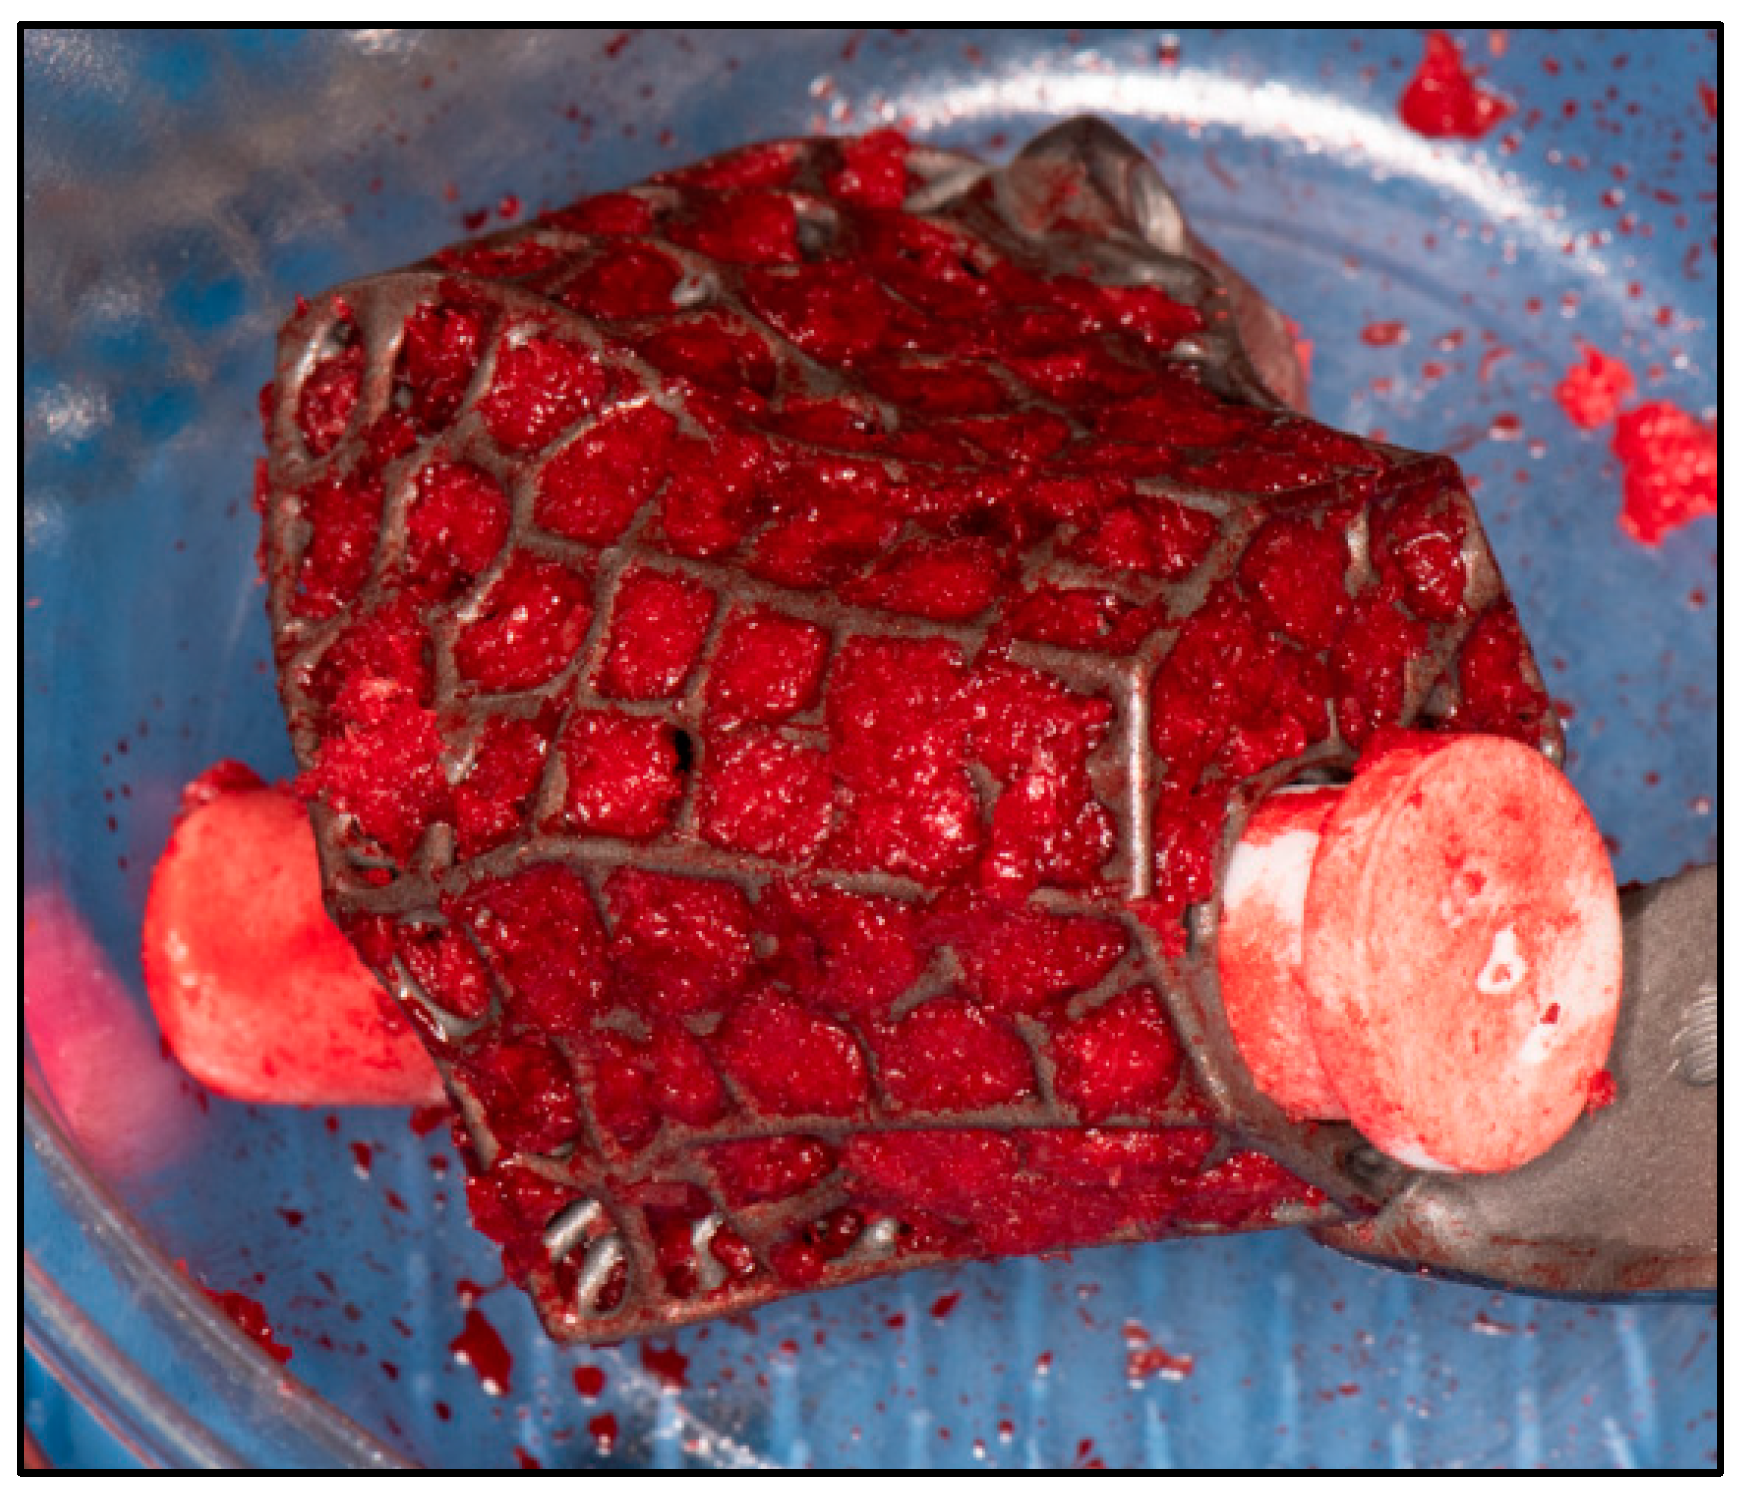

2.2. Surgical Technique